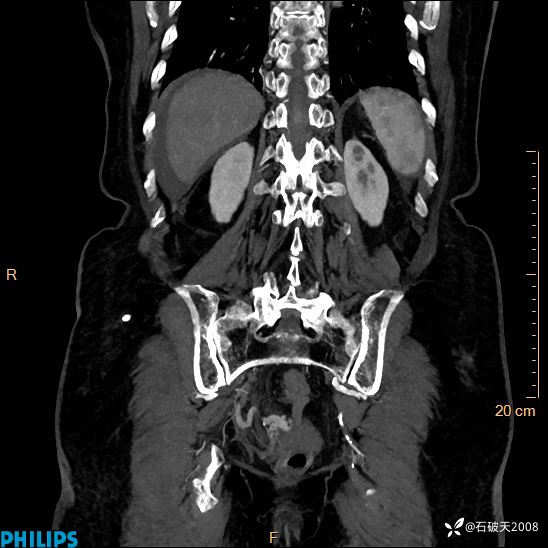

女82岁 主 诉:腹痛半月,加重3天

现病史:半月前患者无明显诱因出现腹痛,上腹部、下腹部间断隐痛,进食后明显,腹胀,大便干,无反酸、烧心,无恶心、呕吐,无腹泻、发热,无咳嗽、咳痰,无心慌、胸闷、无头痛、头晕,无粘液脓血便等症状,患者就诊XXXX医院,给予中草药治疗(具体药物不详)治疗,效差,3天前患者腹痛较前加重,上腹部、下腹部间断隐痛,伴间断性绞痛,今为求进一步诊治来诊我院,门诊以“腹痛”为诊断收住院,自发病来神志清,精神差,饮食差,睡眠一般,小便正常,体重无明显变化。

平扫